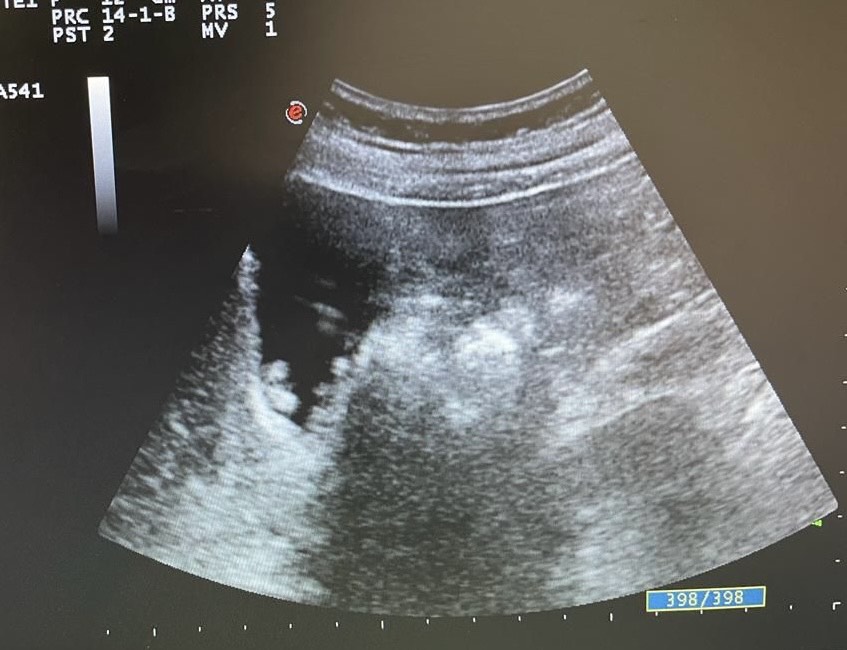

Por primera vez en 23 años de consulta miré las imágenes ecográficas. Y me asaltó la duda, ¿colelitiasis?

Mentalmente describí las lesiones, se trata de lesiones múltiples hiperecogénicas y adheridas a la pared vesicular y que no producen sombra posterior.

Repetí la ecografía para confirmar o descartar mi sospecha.

Confirmé que no se trataba de colelitiasis sino que en mi opinión eran múltiples pólipos vesiculares y alguno de ellos cercano a 1 cm de diámetro, sin poder descartar malignidad con la ecografía, por lo que solicité un TC abdominal que informó de un único pólipo vesicular de 6 mm.